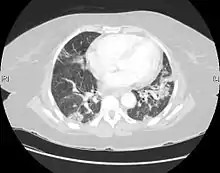

CT scan of a patient with UIP. There is interstitial thickening, architectural distortion, honeycombing and bronchiectasis.

Usual interstitial pneumonia seen on CT scan. Honeycomb fibrosis is seen at the bases of both lungs.

UIP may be diagnosed by a radiologist using computed tomography (CT) scan of the chest, or by a pathologist using tissue obtained by a lung biopsy.

Radiology

Radiologically, the main feature required for a confident diagnosis of UIP is honeycomb change in the periphery and the lower portions (bases) of the lungs.[3]